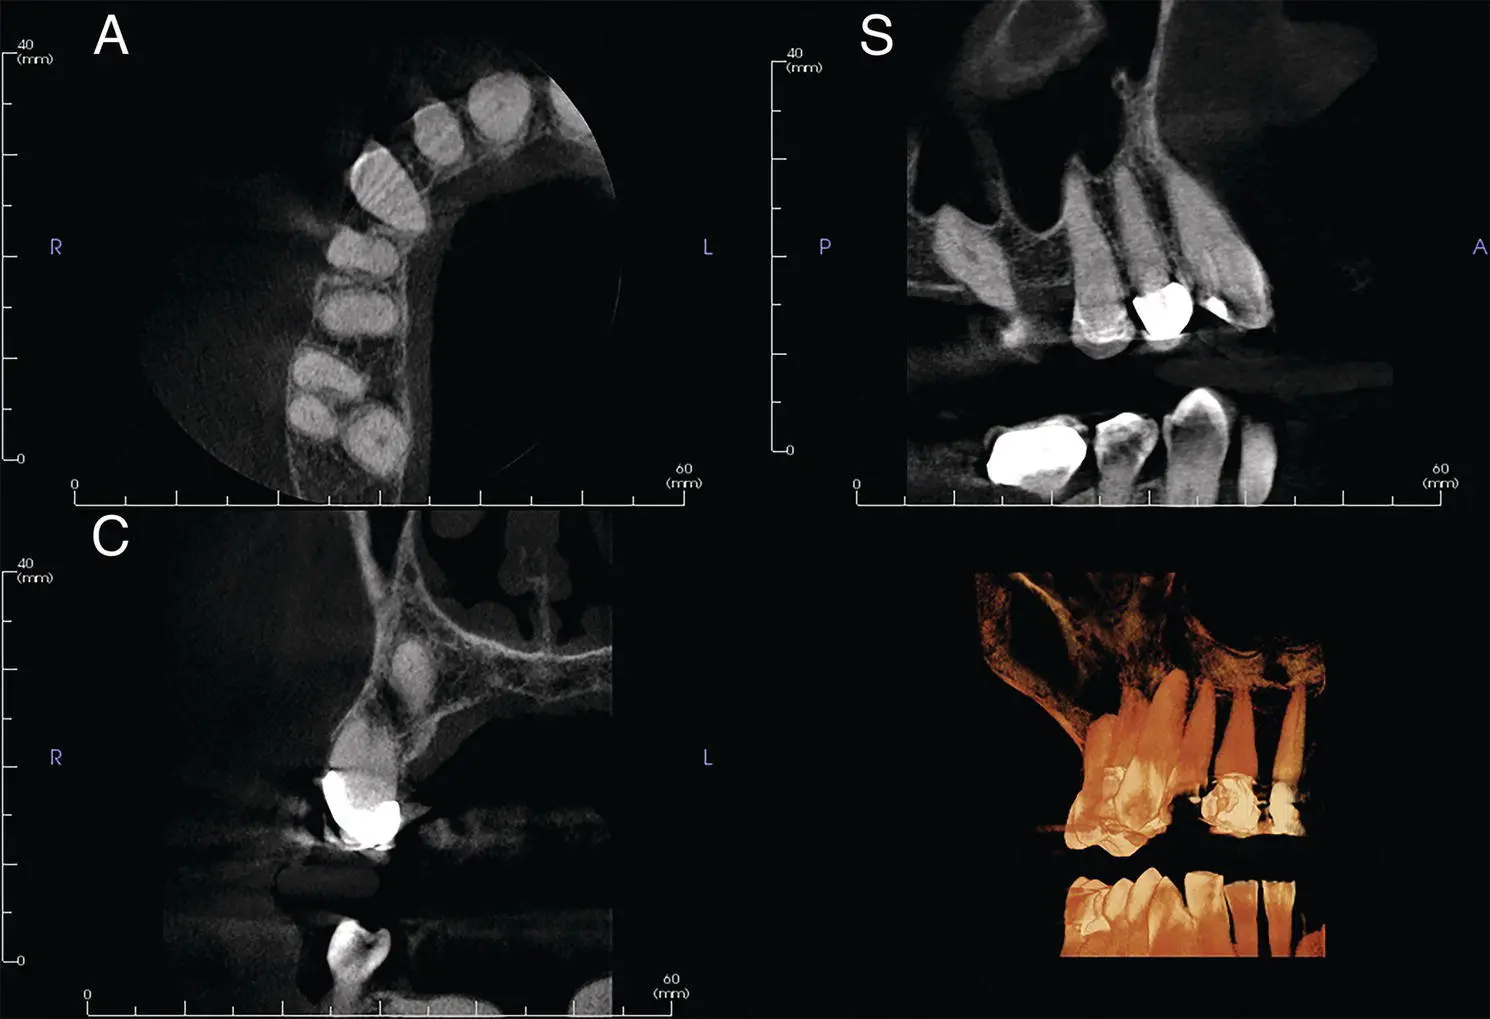

Figure 1.3.(a) 3D rendering of a medium FOV of 8 cm × 8 cm from an anteroposterior (AP) view. (b) 3D rendering of a medium FOV of 8 cm × 8 cm from a lateral view.